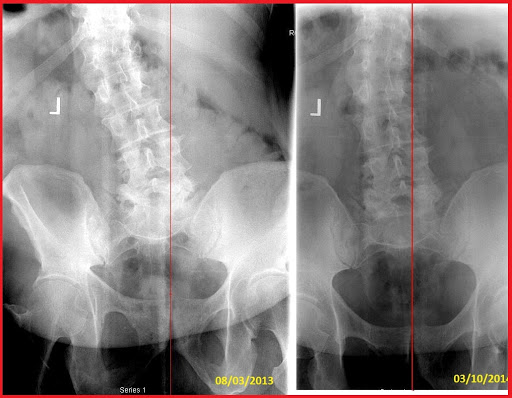

I am 52 years old. I fell when I was in the Marine Corps when I was 19 and have had problems with my neck and lower back ever since. It has not kept me from living life and having a lot of fun but it can get very tiring always having neck and back pain and always feeling like something is wrong. I have had two different fusions (surgery) on my neck at different times trying to relive the pain. I always walk around popping my own neck trying to get the pain to stop. The pain had started getting worse again and was starting to think I was going to end up back under the knife. My daughter, who is an athlete, met and started getting treatment from Dr Lin a year or so earlier encouraged me to let him check me out. I felt immediate relief from the first adjustment but I don’t think I realized just how much pain I was in until about 10 min after I left when I had a very unusual sensation to cry from the relief that I felt. That’s when I knew absolutely that something was better. I have only been getting regular adjustments for about two months but a lot has changed. I don’t walk around feeling like I need to pop my neck all the time. I have better work outs. I can lift more weight and can do more work than I have been able to in a long time. I just feel better all around, not just my neck. I might not be able to explain scientifically what’s going on but I can absolutely tell how much better my life is. I believe if I had this kind of resource in my life earlier I may not have had to have the surgeries I already got.